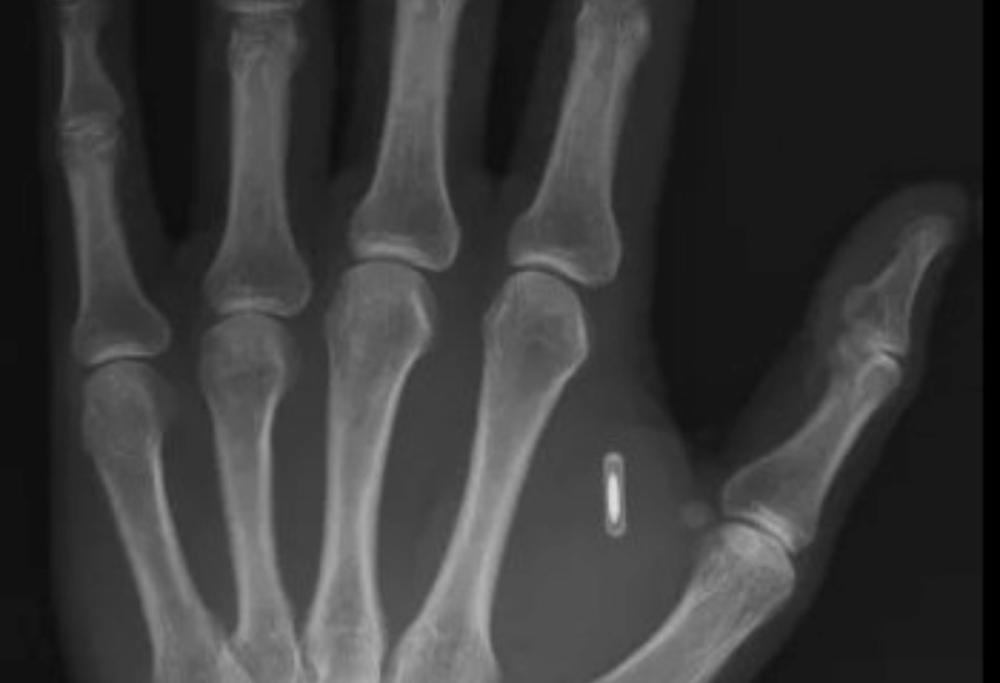

Un prestigiatore e scienziato cinese si è fatto impiantare un chip RFID nella mano per alcuni trucchi di magia.

L'obiettivo iniziale era controllare a distanza il telefono di uno spettatore grazie all'oggetto metallico. Tuttavia, l'esperimento si è rivelato controproducente sia dal punto di vista scenico che tecnico.